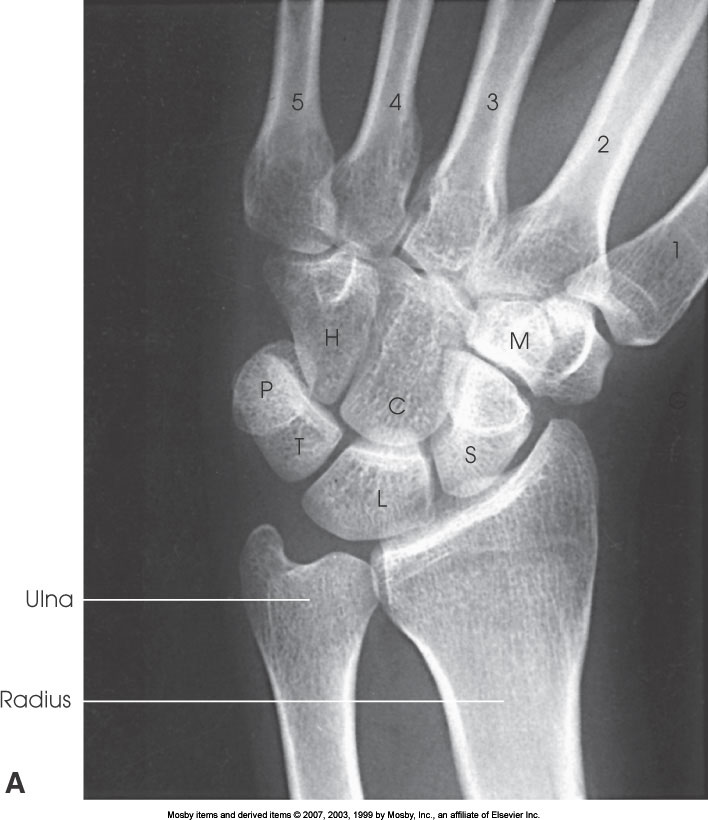

What position is demonstrated?

PA Wrist